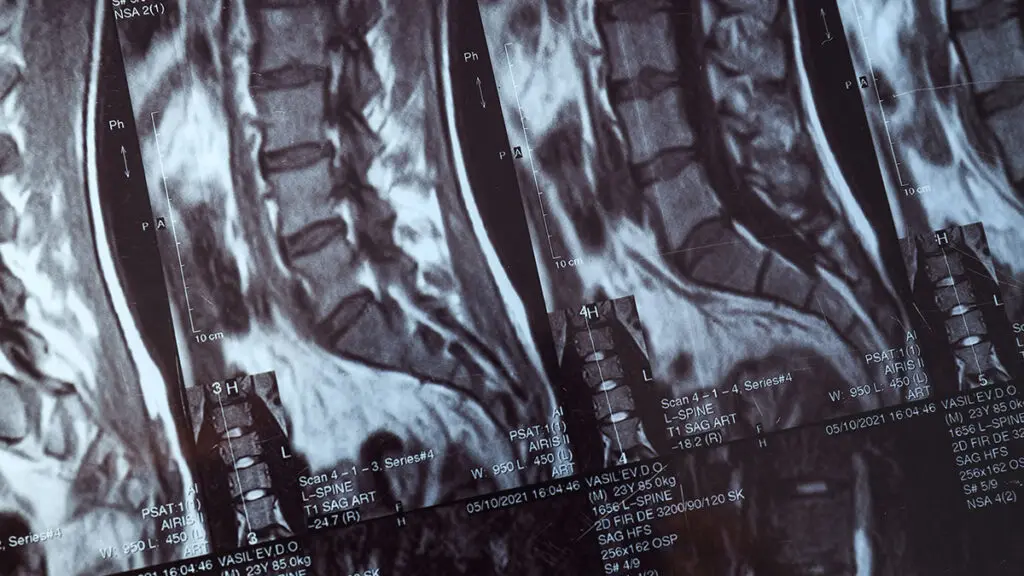

La termoablazione dolore schiena rappresenta una delle tecniche mininvasive più efficaci per il controllo del dolore cronico vertebrale. Global Spine Solutions offre a Roma procedure di termoablazione dolore schiena eseguite da neurochirurghi specializzati, guidate da imaging fluoroscopico o ecografico per la massima precisione e sicurezza nel targeting delle strutture nervose coinvolte.

Il trattamento con termoablazione dolore schiena agisce modulando la trasmissione dei segnali dolorosi lungo le fibre nervose, con effetti duraturi (6-24 mesi) senza controindicazioni sistemiche e senza le problematiche legate all'uso prolungato di analgesici. La procedura si effettua in regime ambulatoriale o in day surgery con rapido ritorno alle attività quotidiane.